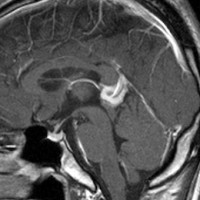

2000年頃の例です。閉塞性水頭症を併発する松果体部germinoma:左のMRIは発症時のものです。定位的生検術で確定診断して脳室ドレナージを留置しました。1コースのICE化学療法直後,生検術から6日目のMRI(中央)では腫瘍はほぼ消失し,水頭症は改善したのでドレナージを抜去しました。4コースの化学療法後(右側)に24Gyの全脳室照射を加えました。